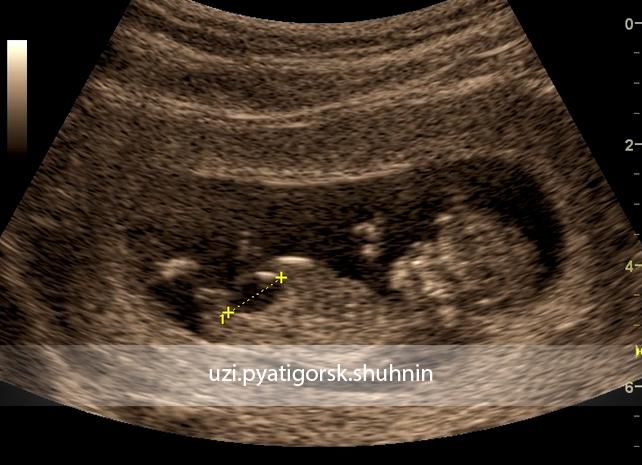

В некоторых случаях во время УЗИ диагностики у беременной женщины обнаруживается увеличенный мочевой пузырь у плода. Если размер органа увеличивается свыше 8 мм, то врач диагностирует о мегацистисе. Но для точного определения болезни, женщине предлагают пройти исследование везикоцентез, при котором через плаценту прокалывают стенку мочевого пузыря, чтобы обследовать мочу ребёнка. Раннее выявление болезни предотвращает дальнейшее ее развитие.

Мегацистисом называют увеличение у плода во время внутриутробного развития мочевого пузыря в продольном размере (больше 8 мм). Кроме этого увеличивается соотношение этого параметра к копчико-теменному размеру (составляет больше 10,4%, при норме — 5,4%). Мегацистис чаще всего обнаруживают на ранних терминах беременности (10-15 неделя) в 0,06-0,19% случаев.

На ультразвуковом исследовании мочевик визуализируется в виде грушевидного или округлого образования. Орган имеет тонкие стенки, расположен в нижней области туловища и увеличивается в размерах в течение беременности матери.

Для определения его размеров необходимо принимать во внимание его наполненность. В случае отсутствия эхотени, рекомендовано проведение УЗИ по истечению 30−40 минутного периода. Врожденные и приобретенные патологии, пороки развития мочеполовой системы помогает обнаружить скрининговое УЗИ.

Мочевой пузырь плода на УЗИ проявляется как тонкостенное образование в нижних участках туловища, имеющее округлую или грушевидную форму. Его размер увеличивается на протяжении беременности. Для оценки размера нужно учитывать возможность его опорожнения, полный он или нет Если эхотень отсутствует, нужно провести УЗИ через 30−40 минут. Врожденные патологии плода помогает диагностировать скрининговое УЗИ. Нормы показателей для определенного срока сравниваются с полученными при обследовании. По ощущениям оно не отличается от обычного ультразвукового обследования. Выявление аномалий мочевыделительной системы на поздних сроках может повлиять на тактику ведения беременности.